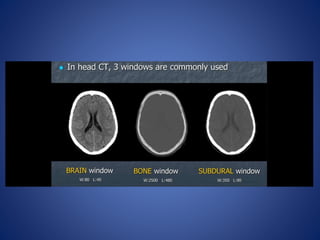

Windowing- the termused for the method of varying density and contrast. Window width-range of CT numbers we select for display Window level-is usually but not always, the central CT number about which the window is chosen

• 44.

Soft tissue filter Bonefilter WL – 50 WW - 200 WL – 50 WW - 400 WL – 600 WW - 1700 WL – 60 WW - 1700